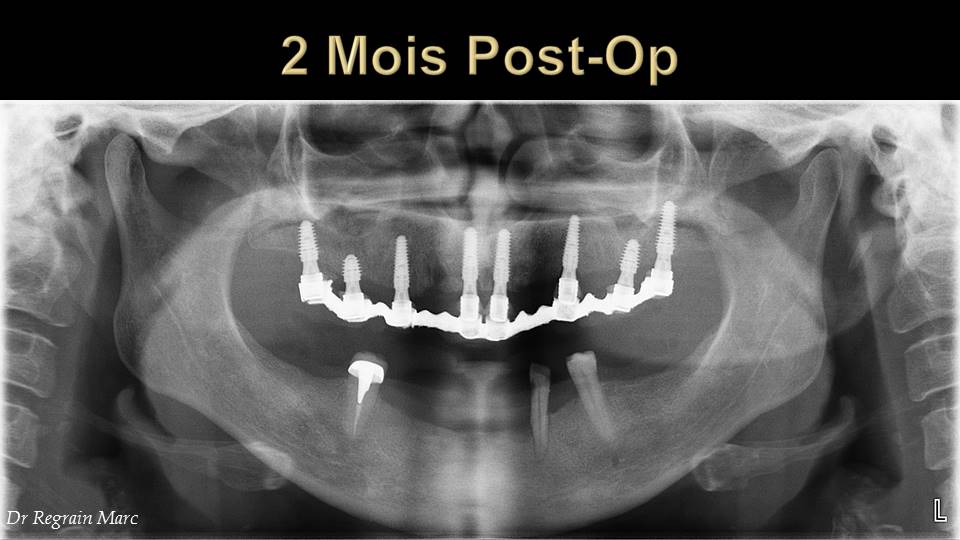

C'était un cas à risque: patiente 49 ans fumeuse depuis x années près d' 1 paquet/jour + prodontite generalisée avec tartre etc. un dentiste lui avait proposé 2 PAC et elle en était malade à l'idée d'avoir des prothèses amovibles et perdre ses dents... Elle aurait du bruxisme la nuit selon ses dires sans pour autant avoir de l'usure importante des faces occlusales. Pour me simplifier la tâche après le det approfondi+ conseils j'ai fait ext des dents max et PAC immédiate en attendant une cicatrisation complète. Entre temps la patiente a fini par arrêter complètement le tabac. J'ai fait un guide avec une DV plus importante que la PAC, qui lui permettrait de serrer moins fort les machoirs par la suite. CBCT avec guide, choix des implants (anthogyr axiom px 4 de diamètre et 10mm de long sauf en postérieur à 8mm et 5,2mm de diamètre.)

Sous forage d'un foret pour tous sauf pour les 2 posterieur j'ai sous foré de 2 diamètre (4mm). Je n'ai pas utilisé d'osteotomes pour compacter ou faire du summers pour le 1mm final dans le sinus (à peine 8mm de hauteur d'un côté) malgré tout je n'ai eu un blocage que à 15N pour les 2 deniers implants larges. Les autres bloqués à 35N. Les 2 implants du secteur antérieur sont angulés d'environ 20 degrés en vestibulaire pour suivre l'axe de la crête. J'ai aussi légèrement vestibulé l'axe des prémolaires en m'appuyant sur la tolérance d'axe de rattrappage avec les multiunits.

J'ai perdu trop de temps à faire un lambeau d'épaisseur total car je n'ai pas l'habitude mais ca devrait s'accélérer avec le temps j'espère. Pose des piliers MU, sutures simples avec fil 4.0 resorbable, empreinte à l'impregum soft et PEI à ciel ouvert. Pose des capuchons et mordu au silicone à la dv du guide mesuré avec un compas. Antalgiques nvI + celestene 6mg/j pour 3 jours + ATB. A 72h pose du bridge et reglage de l'occlusion. Les sutures sont laissées pour l'instant.